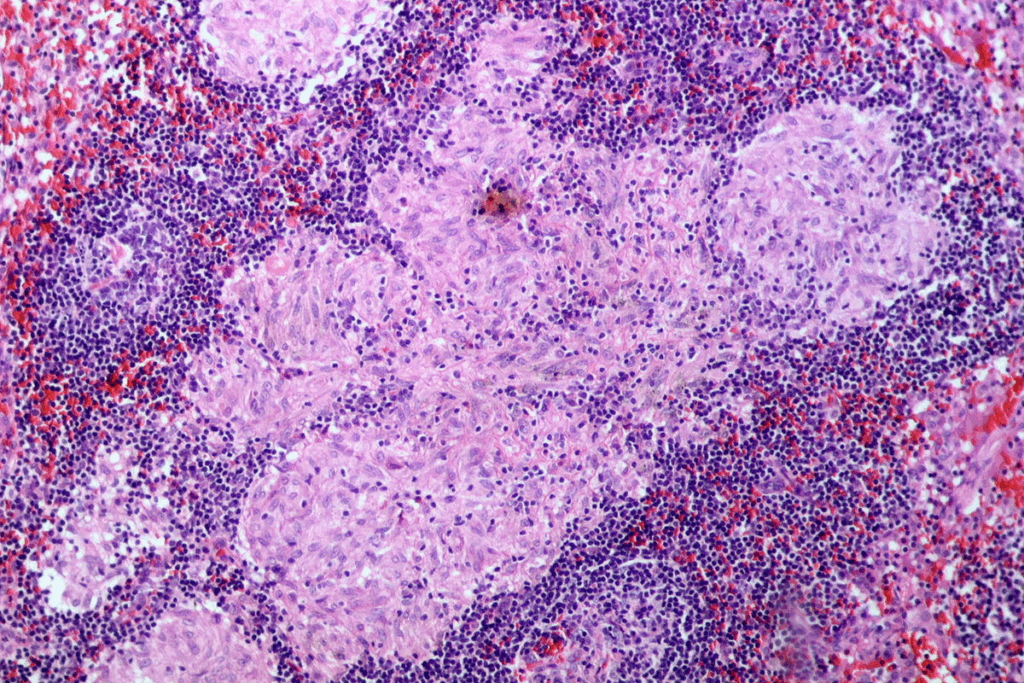

Diagnostic Approaches for Mucosal Disorders

Diagnosing oral mucosal disorders needs a detailed approach. This includes clinical exams, tissue analysis, and sometimes more tests. We use different tools to find the cause of oral lesions.

Diagnostic Approach | Description | Clinical Application |

Clinical Examination | Visual inspection and palpation of oral mucosa | Initial assessment of lesions and mucosal changes |

Histopathological Analysis | Microscopic examination of tissue samples | Definitive diagnosis of mucosal disorders |

Immunohistochemistry | Identification of specific proteins in tissue samples | Diagnosis of autoimmune disorders and cancer |